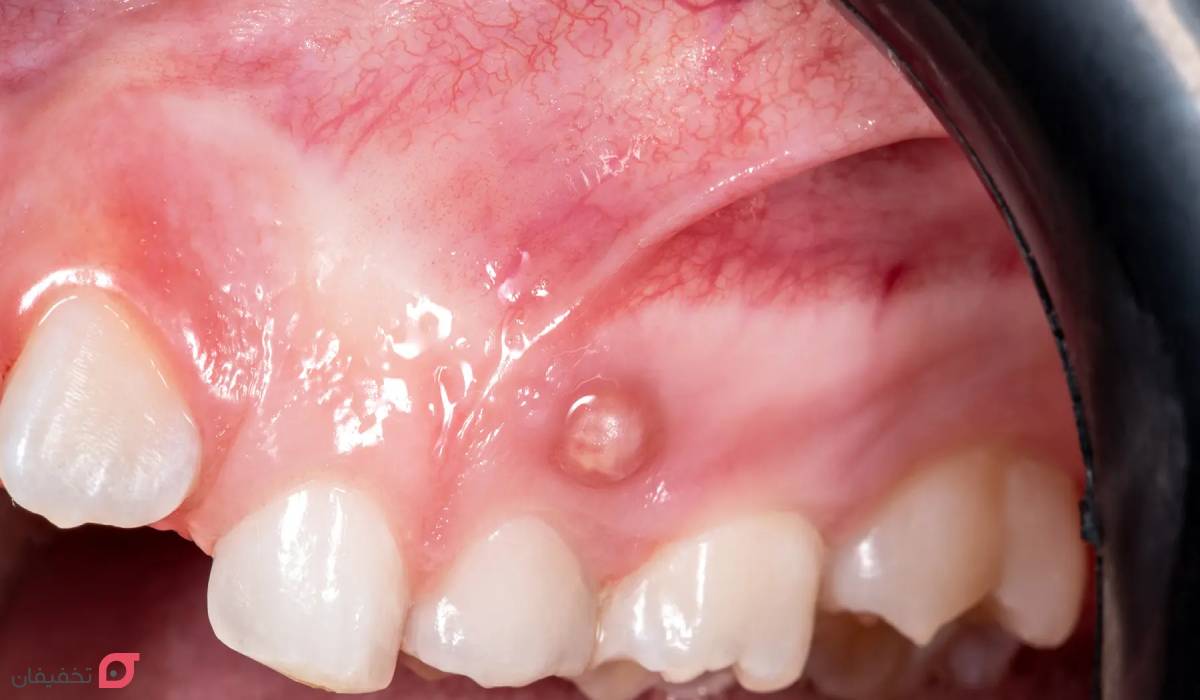

آبسه دندان یعنی جمع شدن چرک در اطراف دندان یا لثه به خاطر عفونت باکتریایی. زمانی که میکروب ها وارد بافت نرم اطراف ریشه دندان یا لثه می شوند، بدن برای مقابله با آن ها چرک تولید می کند و این باعث ورم، درد، التهاب و حتی تب می شود. آبسه در اصل نشانه ای است از اینکه بدن در حال جنگیدن با عفونت است.

این عفونت ممکن است در اطراف ریشه دندان، بین لثه و دندان یا در بافت های اطراف آن شکل بگیرد. اگر آبسه درمان نشود، چرک درون آن بیشتر می شود و ممکن است به استخوان فک یا دیگر بخش های بدن منتقل شود. برای نمونه، کسی که دندان پوسیده خود را مدت ها بدون درمان رها کرده است، احتمال زیادی دارد دچار آبسه شود.

آبسه ها که گاها با آفت دهان اشتباه گرفته می شوند، بر اساس محل ایجاد و دلیل عفونت به چند نوع تقسیم می شوند:

- آبسه سطحی لثه: روی سطح لثه ایجاد می شود و اغلب بین دندان ها دیده می شود. علت اصلی آن گیر کردن غذا یا جسم خارجی مثل پوسته تخمه یا تکه ای گوشت در لثه است.